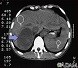

Imaging tests of the abdomen may include:

- CT scan